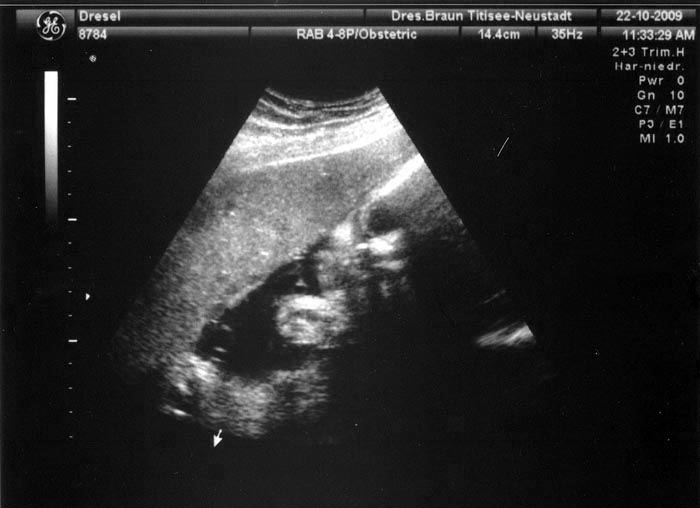

8. Ultraschallaufnahme